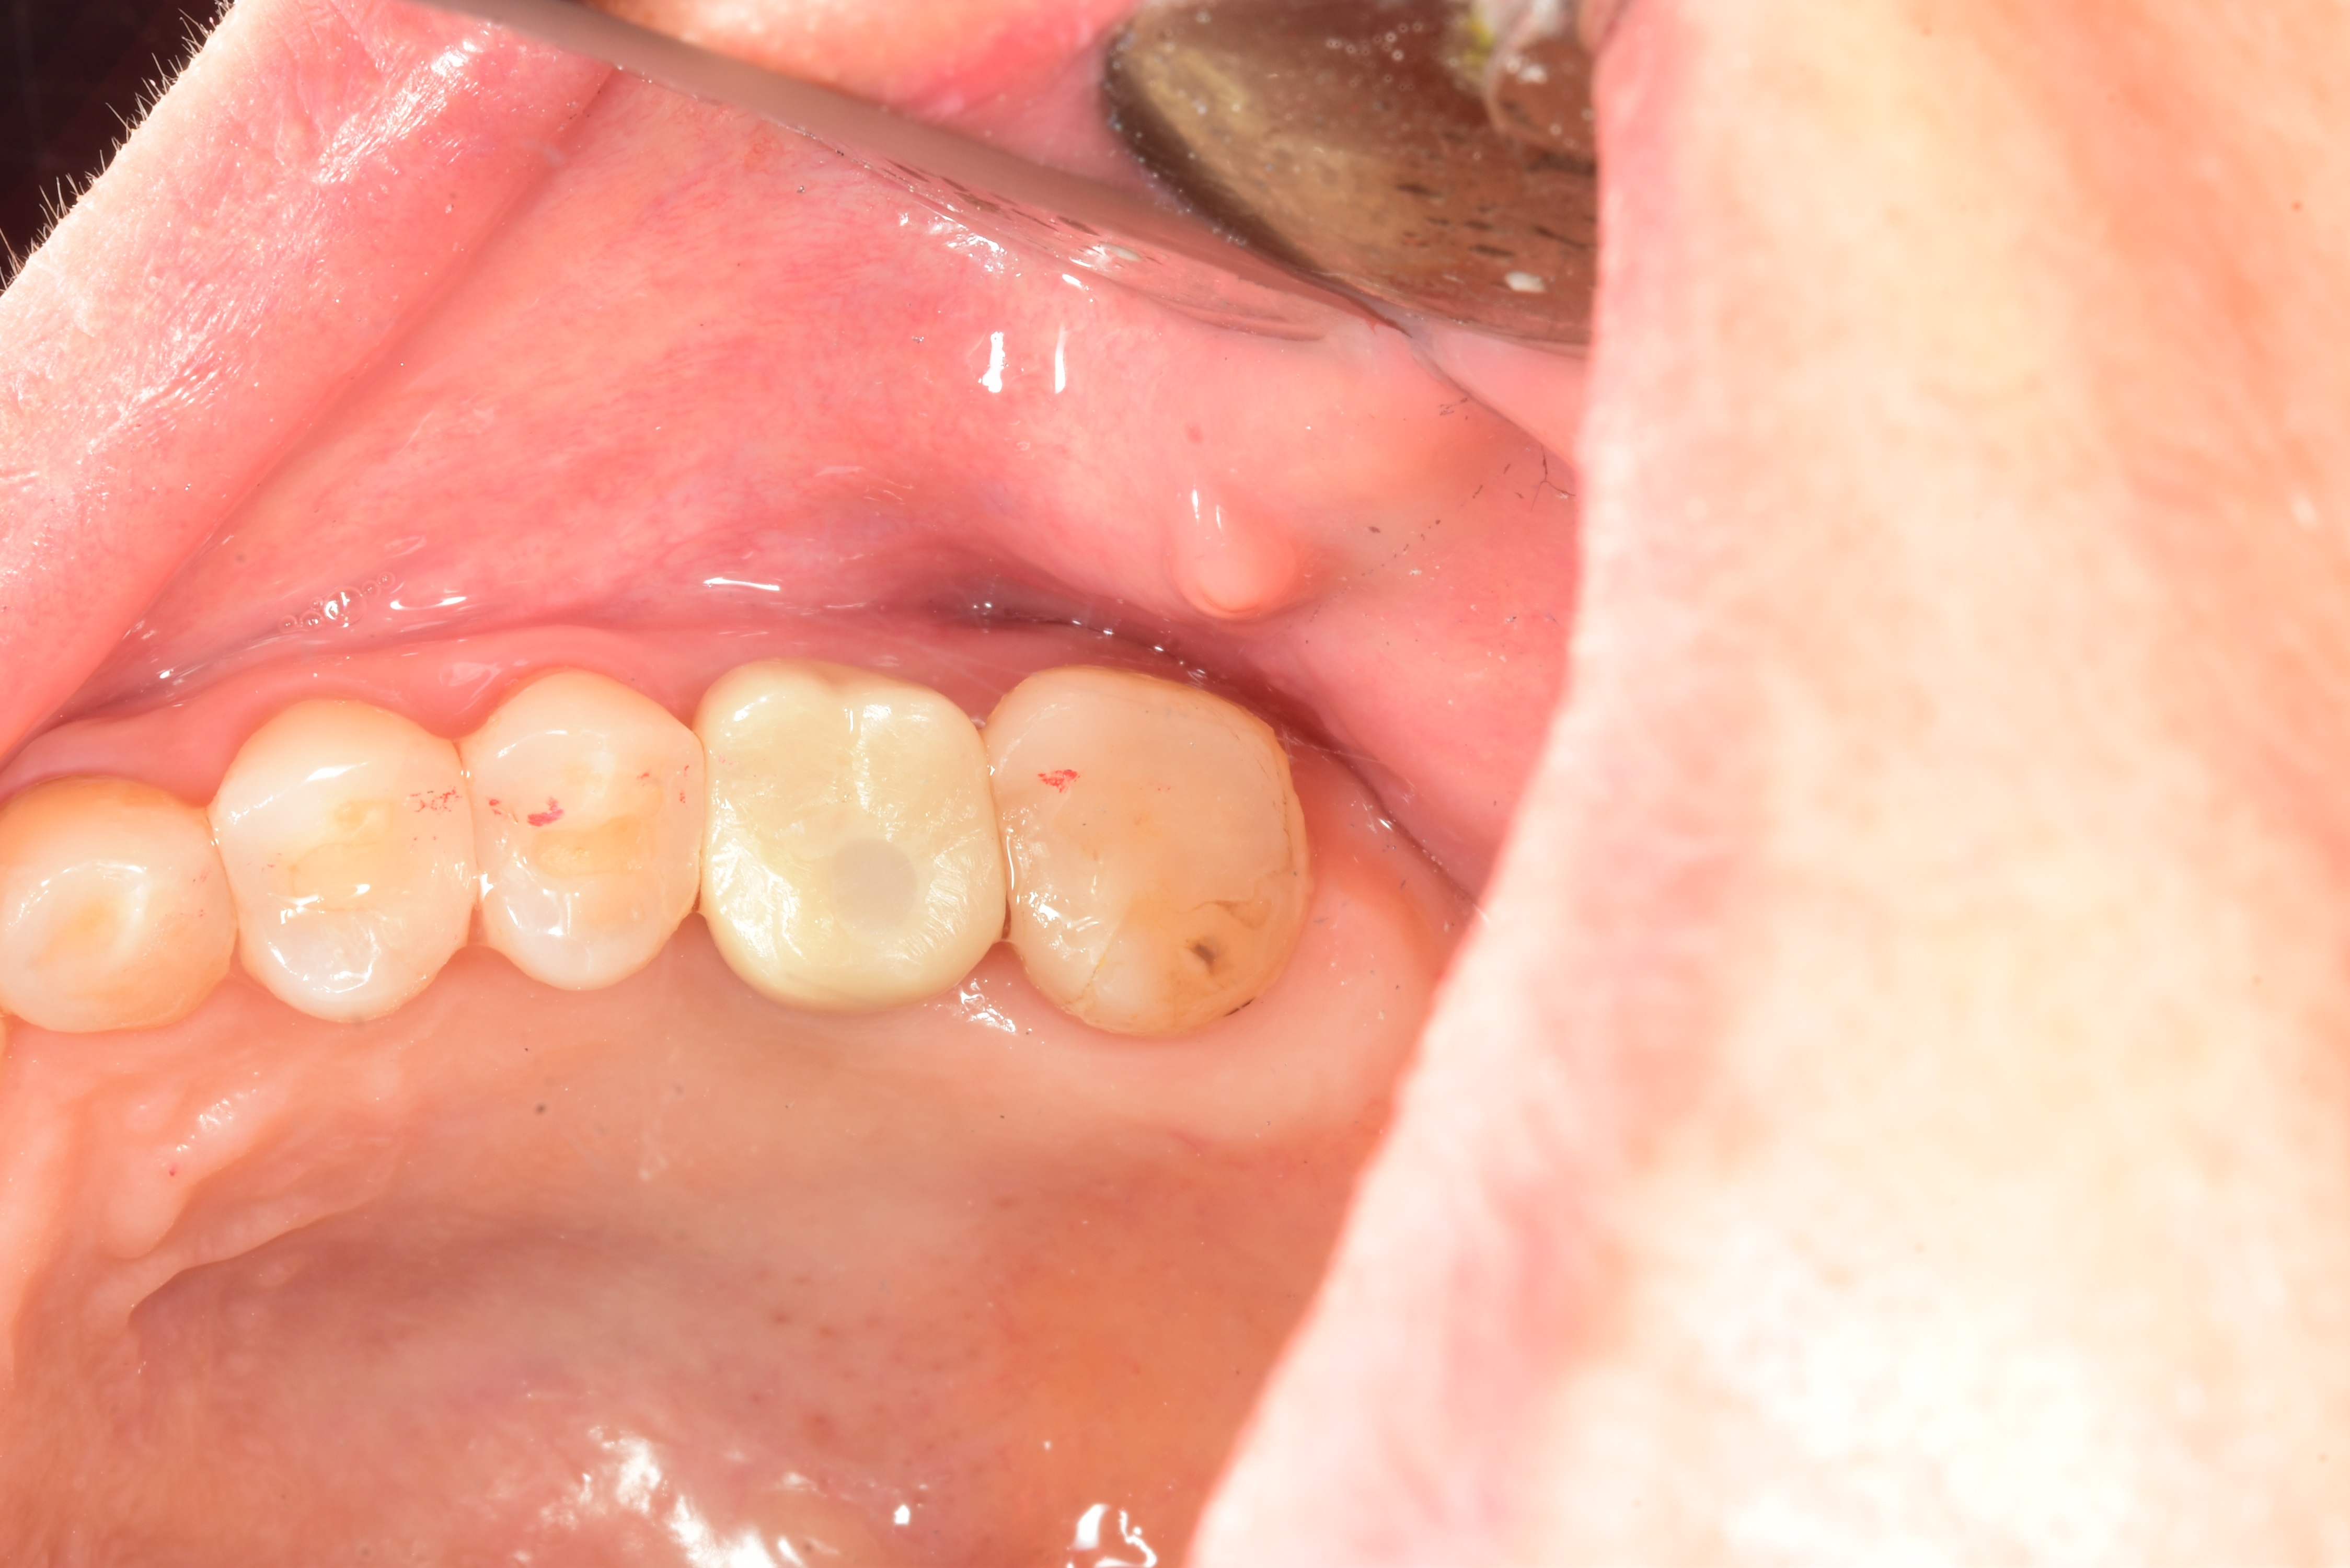

案例四

使用數年的假牙,牙根萎縮,建議拔除及植牙

醫生透過電腦斷層評估骨頭狀況決定植入的植體所放的寬度與深度

植入植體,並鎖上癒合螺帽

2-3個月癒合,7-10天完成假牙 ,試戴、調整咬合高度並鎖上,封填,完成